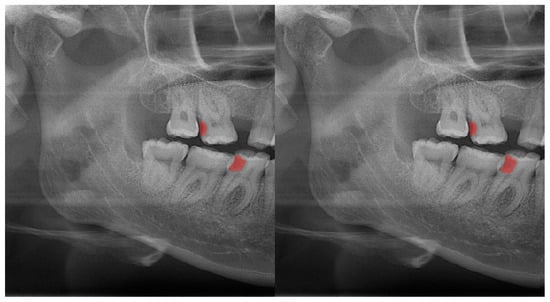

Figure 3.

Automatic segmentation of the carious lesions at the upper-left second molar and lower-right first molar. Manual segmentation (left) as well as automatic segmentation (right) can be seen above.

In Figure 8, a more successful automatic segmentation is observed at the maxillary right third molar than the maxillary left third molar, and a missing segmented area in the form of a notch is observed. As most of the upper third molars were superimposed on the floor of the maxillary sinus and zygomatic process of the maxilla, erroneous segmentations were inevitable. In Figure 9, an erroneous automatic segmentation at the mandibular left second molar due to the superimposition between the mandibular left first and mandibular left second premolars can be seen.